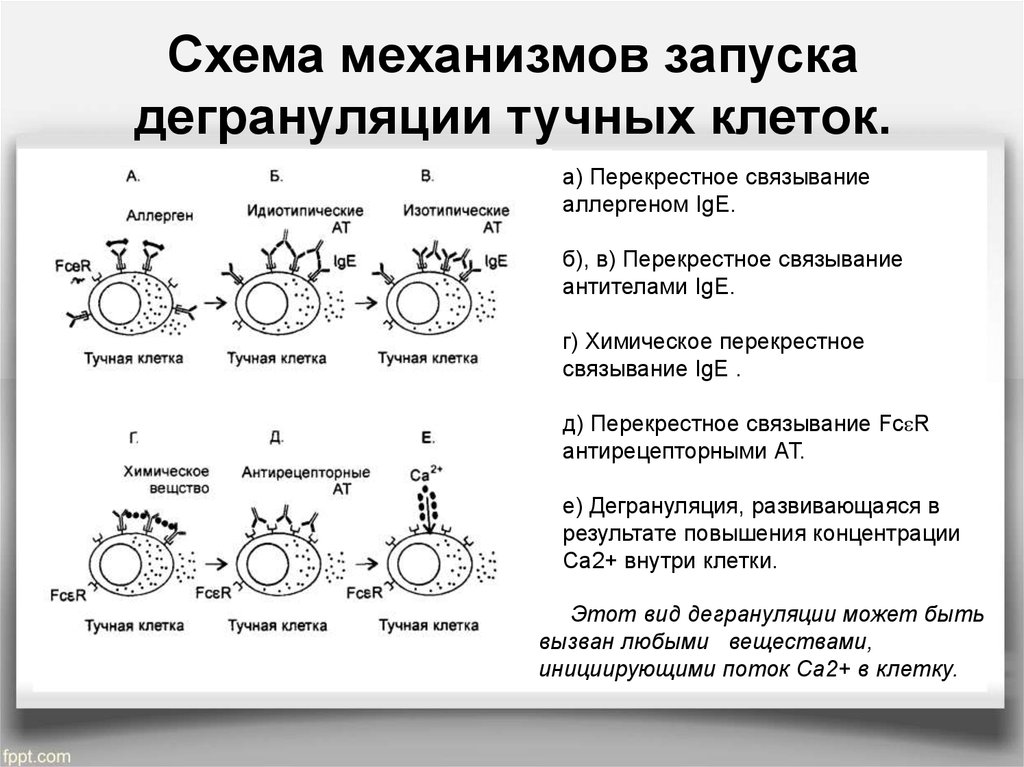

Диплопия: механизм развития и методы лечения